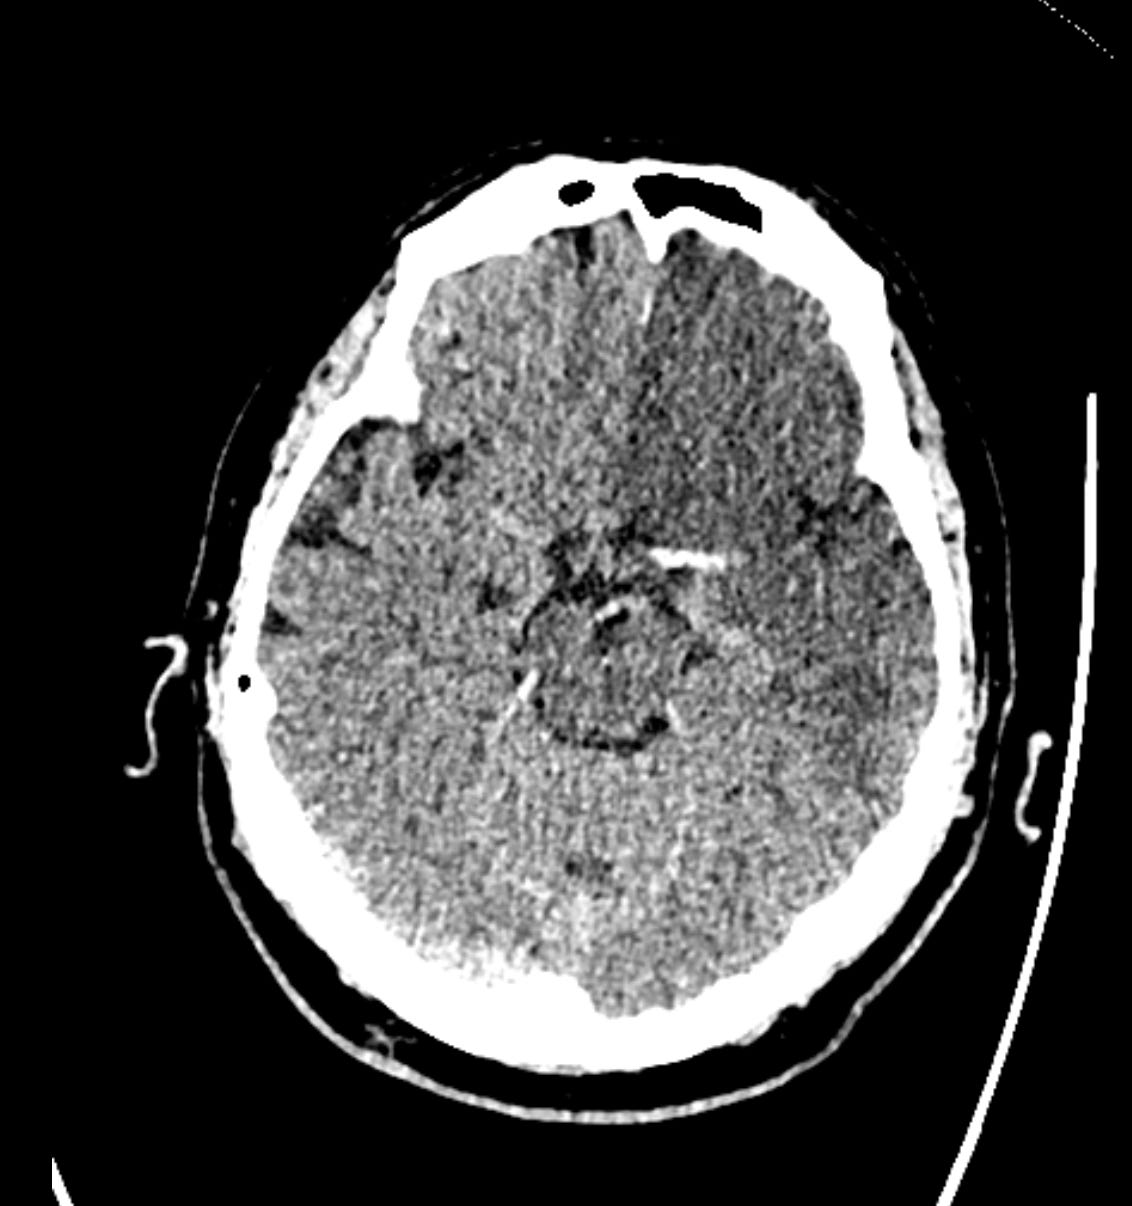

A non-contrast CT head is shown below.